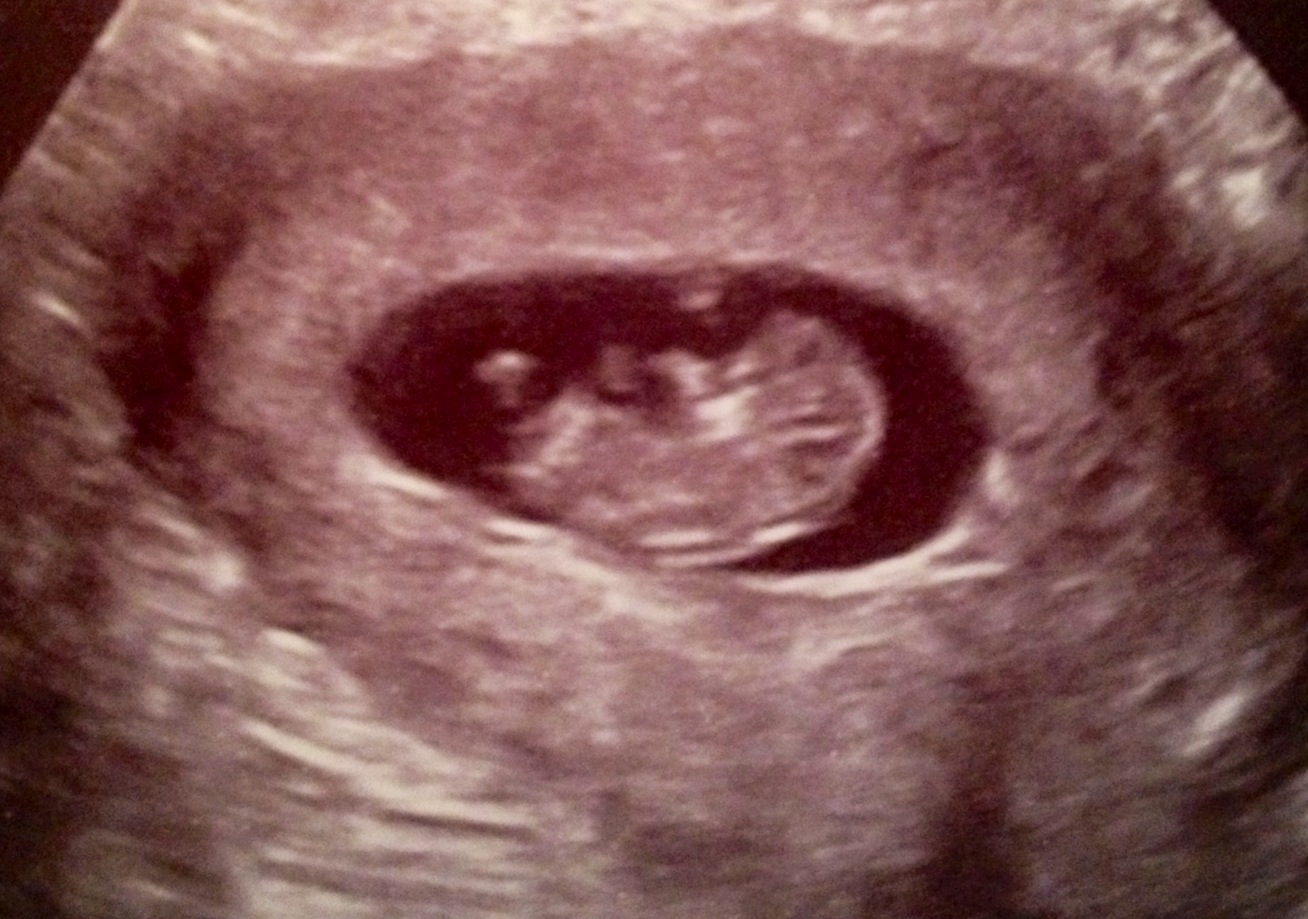

I don't know much about nub shots and if they can be seen in these pics or not. Or if they'd even be accurate this early.

Thoughts are much appreciated! :)

Attachment 23425